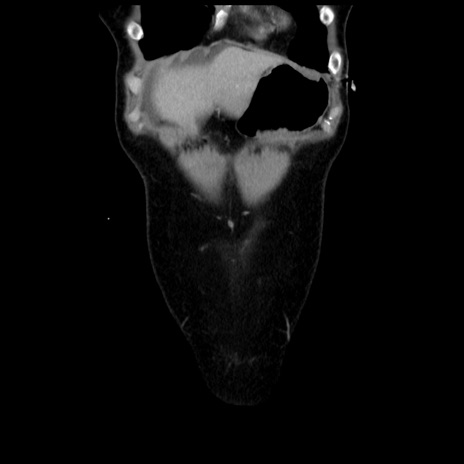

横断像